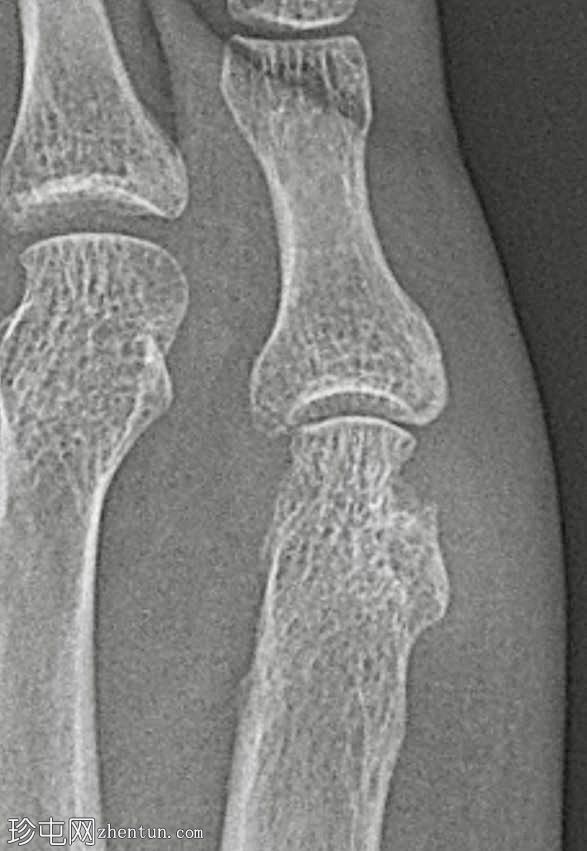

骨质疏松伴皮质变薄

左侧(正位、斜位)和右侧(正位斜位)第五跖骨头关节旁骨侵蚀

边界不清

局部软组织肿胀

侵蚀通常位于跖骨头跖侧,提示炎症和生物力学因素均有影响

斜位X线片、放大倍数和锐化算法对于显示这些侵蚀至关重要

边界不清提示疾病活动期